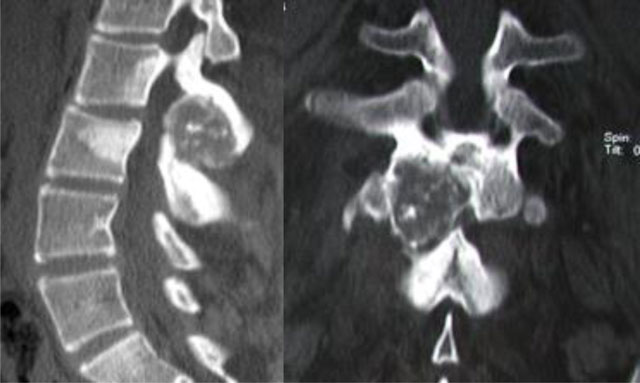

Figure 2

Osteoblastoma of L2. CT scan shows an expansive osteolytic lesion of the L2 neural arch with central calcification, sclerosis of the body and the neural arch of L2 and L3.